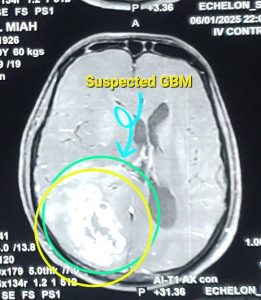

জিবিএম (Glioblastoma Multiforme - GBM)

GBM (Glioblastoma multiforme) হলো মস্তিষ্কের একটি অত্যন্ত আক্রমণাত্মক এবং দ্রুত বর্ধনশীল ক্যান্সার। এটি গ্রেড IV টিউমার হিসেবে শ্রেণীবদ্ধ, যা সবচেয়ে গুরুতর। GBM-এর চিকিৎসায় সার্জারি একটি গুরুত্বপূর্ণ ভূমিকা পালন করে, এরপর সাধারণত রেডিয়েশন থেরাপি এবং কেমোথেরাপি দেওয়া হয়।